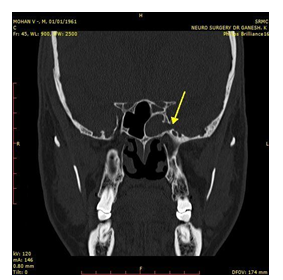

A 53year old gentleman came to the OPD with chief complaints of clear watery discharge from the left nasal cavity for the past one and a half months. Examination showed clear watery discharge when the patient bent forward indicative of cerebrospinal fluid. Diagnostic nasal endoscopy showed an active CSF leak from the sphenoid recess. CT of paranasal sinuses showed mucosal thickening in the left side of the sphenoid sinus and left posterior ethmoidal sinus with obstruction of sphenoethmoidal recess (Figure 1). MRI Cisternography showed evidence of bony defect in the left lateral wall of the sphenoid sinus measuring 9 x 10mm (CC x AP) with hernia ion of the small portion of the medial left temporal lobe with dura & CSF- suggestive of left medial temporal lobe encephalocele (Figure 2 & 3).

Figure 1 CT PNS showing homogenous soft tissue shadow in the left sphenoid sinus. The arrow showing the area of the Sternberg’s canal.